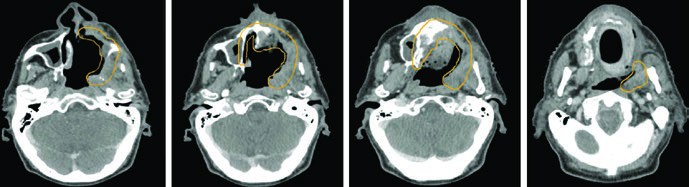

Alguns padrões de disseminação merecem atenção especial. ENB, SNUC e SNEC surgem na cavidade nasal superior e invadem facilmente a lâmina cribriforme em direção à fossa craniana anterior. Essas regiões precisam ser incluídas no volume alvo. Já os cânceres do seio maxilar podem invadir a cavidade nasal pela parede medial porosa, a gengiva maxilar pela parede lateral do antro, a fossa infratemporal ou pterigopalatina por extensão posterior, ou a órbita por extensão superior direta ou via seios etmoidais.

A TC de alta resolução dos seios paranasais com contraste IV e cortes finos de 1–2 mm é ideal para visualizar erosão cortical óssea precoce. A RM com contraste IV e sequências com supressão de gordura, em cortes finos, é superior para avaliar extensão em partes moles, extensão intracraniana, invasão perineural e envolvimento dos forames e canais dos nervos cranianos. O PET/CT complementa o estadiamento ao identificar linfonodos suspeitos e doença metastática.

A RM deve ser usada em todos os casos para auxiliar o delineamento, exceto quando contraindicada. Carcinomas adenoides císticos são altamente neurotrópicos, portanto os volumes devem cobrir nervos aferentes e eferentes locais até a base do crânio. ENB surge na cavidade nasal superior e tende a invadir a lâmina cribriforme e fossa craniana anterior precocemente.

| Seio maxilar (CEC) | Superior | Assoalho orbital/base do crânio. RM coronal útil para assoalho orbital. Extensão intracraniana: margem dural de 5 mm |

| Inferior | Palato duro com margem mínima de 10 mm ao redor da doença macroscópica inicial | |

| Medial | Septo nasal para casos lateralizados. Extensão medial além do septo: considerar cobertura de toda a cavidade nasal | |

| Lateral | Fossa infratemporal incluindo espaço mastigatório. Extensão lateral: considerar cobertura ao longo do músculo temporal | |

| Posterior | Fossa pterigopalatina e base do crânio, incluindo fissura infraorbital. Envolvimento posterior: cobrir cursos de CN V2/V3 até a caverna de Meckel | |

| Nervos | Ramos de CN V2, nervo infraorbital e nervos palatinos maiores | |